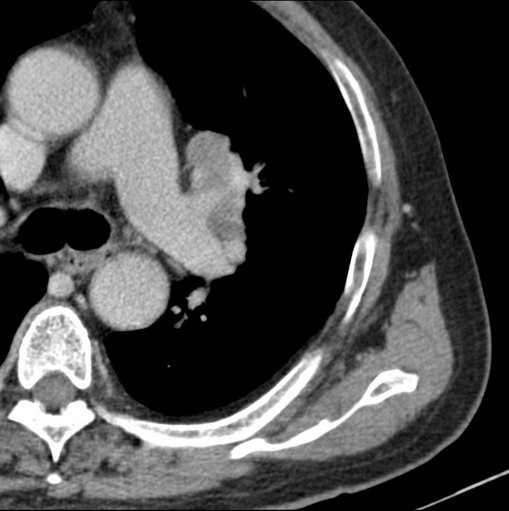

男性患者 81岁 咳嗽 咳痰 咯血

肿块贴近左肺门,包绕左上肺动脉,形态不规则。肿块增强扫描中度强化。纵膈内主动脉弓左旁间隙、气管隆突前、下间隙见多枚淋巴结影。综上考虑左侧中央型肺癌可能性大。图片没有完整上传,尤其是左肺上叶支气管分支层面没有上传,因此不好判断是叶支气管中断还是段支气管中断。另外,下图红色部分所示是“黏液支气管征”吗?